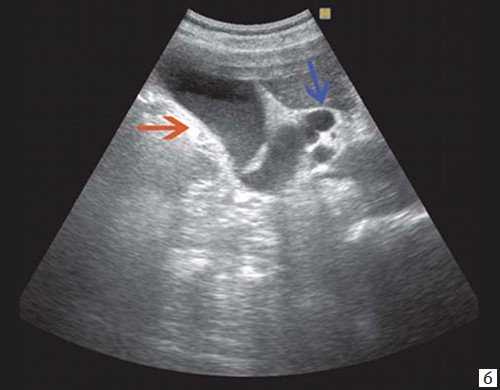

При низком билиарном блоке (обтурация на уровне холедоха, головки ПЖ, БДС) кроме расширенных внутрипеченочных протоков визуализируются расширенные внепеченочные протоки, желчный пузырь увеличен (рис. 2).

Рис. 1. Ультразвуковая картина билиарной гипертензии при механической желтухе.

б) Увеличенный желчный пузырь с густой взвесью (красная стрелка) и расширенный ОЖП (синяя стрелка).

а) Увеличенный желчный пузырь с густой взвесью внутри (красная стрелка) и расширенный ОЖП (синяя стрелка).